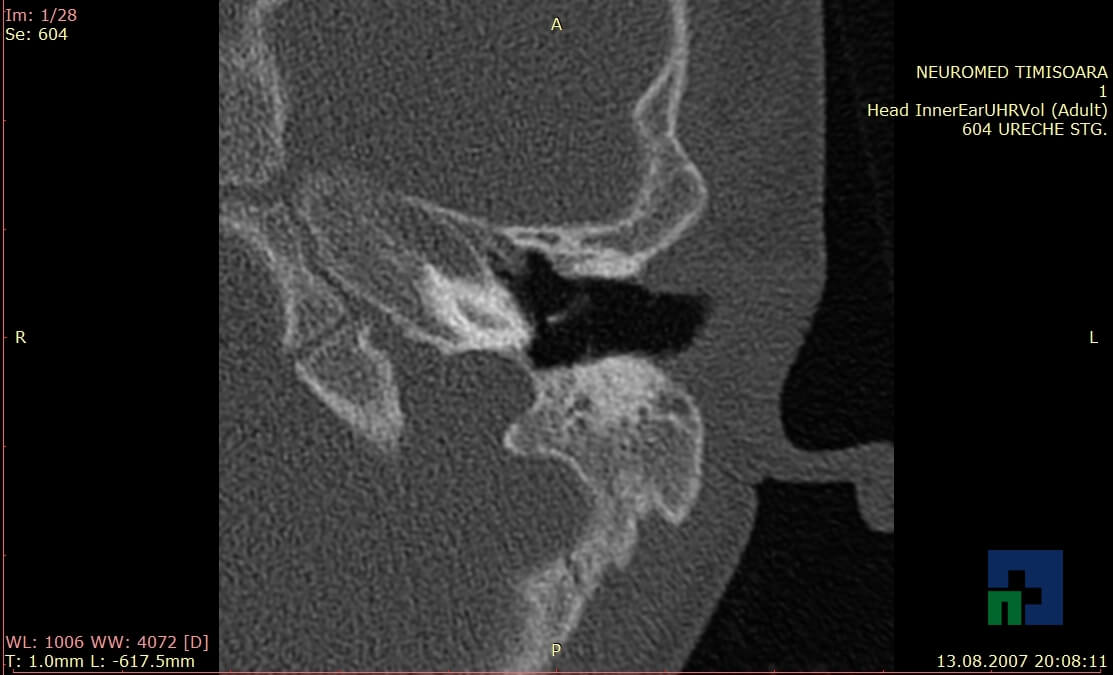

- Diagnosticul traumatismelor de bază de craniu

- Diagnosticul fistulei LCR

- Diagnosticul fracturilor: